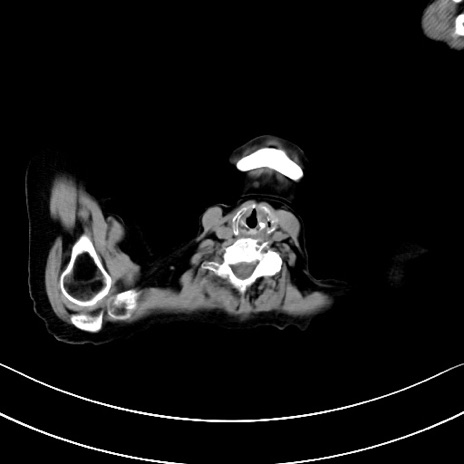

横断像

他院CT